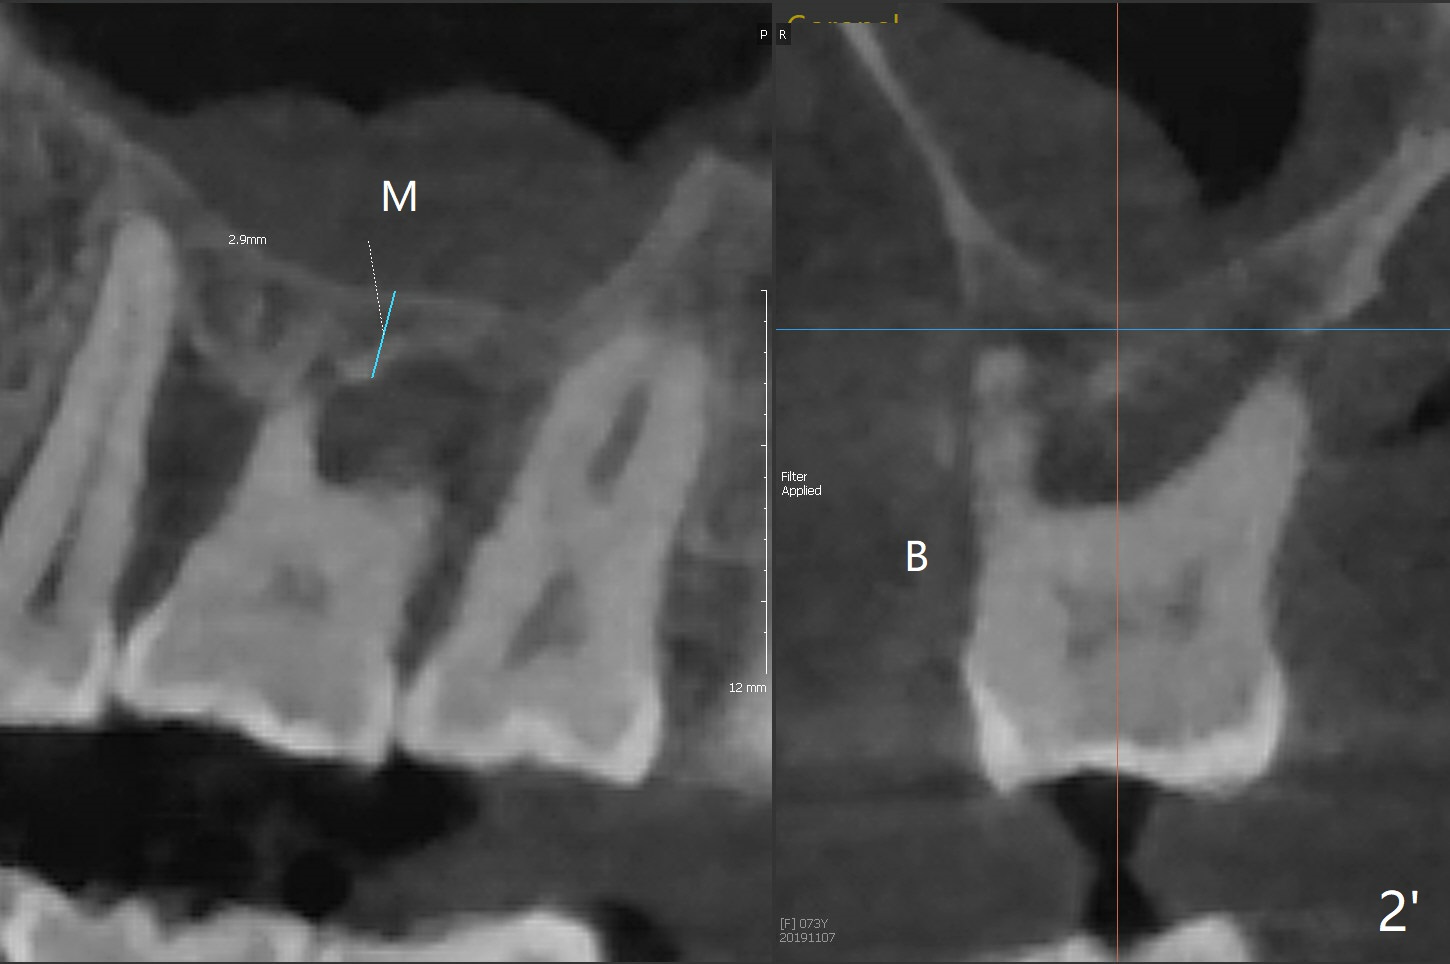

A 73-year-old woman with controlled diabetes has cold and hot sensitivity of the tooth #3. Although the bone loss is striking (Fig.1), mobility is I with the deepest pocket DL ~6 mm. Endo ice induces pain. Extraction and guided immediate implant appears to be the best option (Fig.2 (5x7mm FC)). Note the bone height (2.9 mm) and the thick sinus membrane (M, Fig.2') . B: buccal. Bony defect will be filled with sticky bone and held in place with Cytoplast, while PRF for sinus lift. Because she is afraid of implant, RCT, followed by SRP and possibly periodontal surgery, seems to be viable because of the straight, not-so-narrow canals (Fig.3-5). Due to time constraint, immediate implant will be done free hand. Use IS cassette, since there are 3 and 4 mm stoppers. Prepare FC dummy and water lifter for sinus lift.